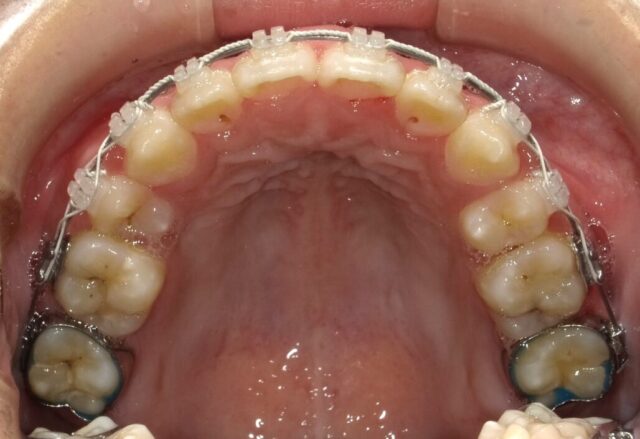

≪上顎咬合面観≫

2023年5月

2023年6月

2023年7月

2023年8月

2023年9月

2023年10月

2023年11月

2023年12月

2024年1月

2024年2月

2024年3月

2024年4月

2024年5月

2024年6月

2024年7月

2024年8月

2024年9月

2024年10月

2024年12月

2025年1月